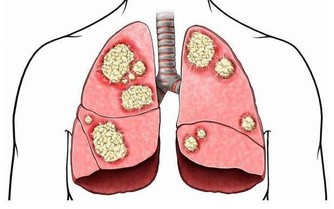

八、鼻子的警示信號

鼻子不靈,同時經常咳嗽,有時甚至呼吸困難,這是肺功能逐步衰退的標誌。

病人首先要注意飲食,戒菸或者控制吸菸量,也不要和經常吸菸的人在一起。

多吃新鮮瓜果和蔬菜,加強體質鍛鍊,防止肺部合併症的發生。